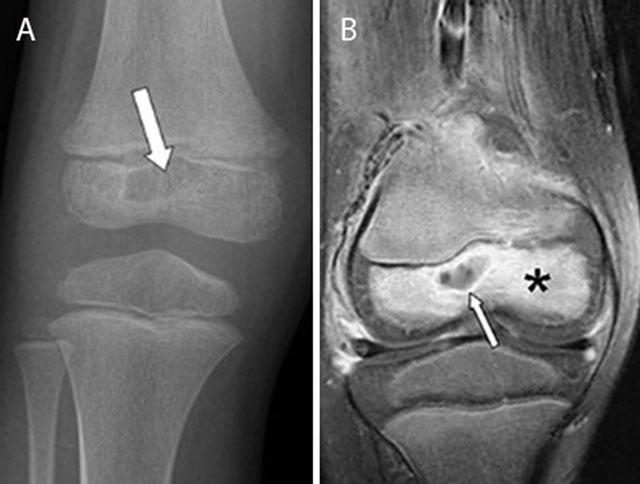

Figure 4

Epiphyseal childhood osteomyelitis of the right knee. Plain radiograph (a) of the distal femur shows a radiolucent lesion with peripheral sclerotic rim (white arrow) in the epiphysis of the distal femur. After gadolinium contrast administration (coronal T1–Fat–Sat WI, (b) the central part of the lesion is non-enhancing whereas there is subtle peripheral rim enhancement (white arrow) with moderate enhancement of the surrounding bone marrow edema.

In rare scenarios, the infection spreads predominantly by the circulus articuli vasculosus of Hunter supplying the epiphysis (Figure 4). This may explain the rare occurrence of epiphyseal childhood osteomyelitis [6].